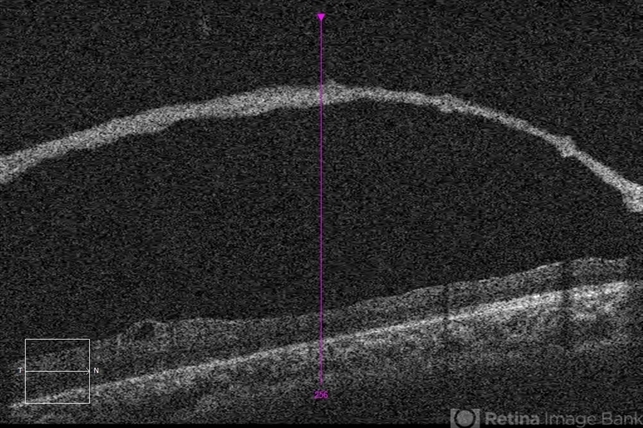

- retinal hole, retinoschisis

Optical coherence tomography system

Zeiss Cirrus 5000 - Description

- 21-year-old male with congenital retinoschisis with bilateral macular involvement and large inner retinal hole OD.